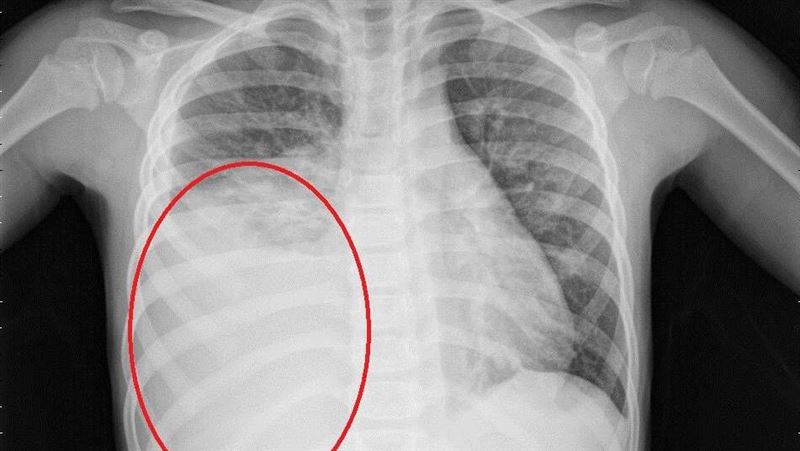

往返中國小心!「大白肺」激增 2招防堵